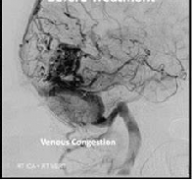

動(dòng)靜脈畸形(AVM),可以說是較復(fù)雜和較危險(xiǎn)的腦血管病變,我們將考慮。Spetzler-Martin分級(jí)系統(tǒng)較初被認(rèn)為是一種外科風(fēng)險(xiǎn)評(píng)估工具,它為AVM大小、位置和靜脈引流模式分配分?jǐn)?shù),通常用于...

Q:腦動(dòng)靜脈畸形因何破裂?有何危害?如何治療? A:腦動(dòng)靜脈畸形亦稱腦血管瘤,非真性腫瘤,系先天性腦血管發(fā)育異常,臨床上有多種類型,其中以動(dòng)靜脈畸形多見,根據(jù)畸形血管...

Q:腦動(dòng)靜脈畸形出血率和死亡率風(fēng)險(xiǎn)高嗎? A:AVM的總體年出血率約2-4%,但這不適用于全部的AVM,部分AVM潛在的解剖和血流動(dòng)力學(xué)相關(guān)特性使其更具有出血傾向。 促使出血的兩類主要...